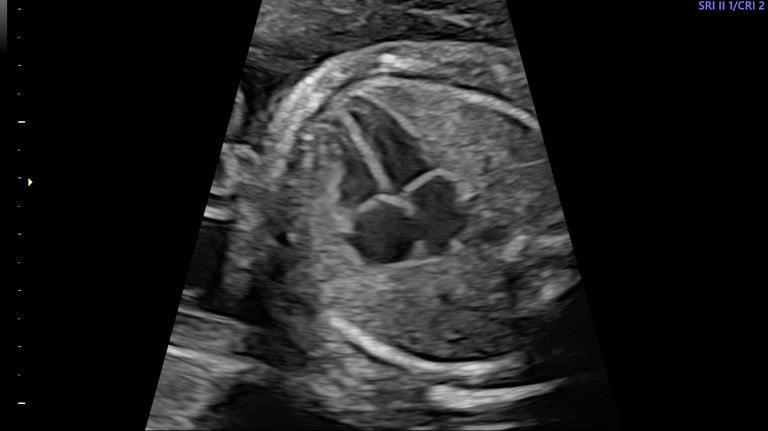

ecografía morfológica primer trimestre (genética y más)

12 - 14 semanas

ecocardiografía fetal

neurosonografía fetal